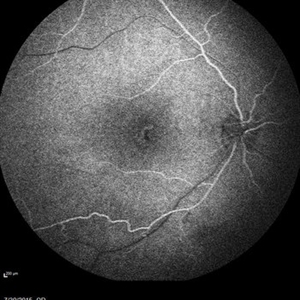

Retinal Dystrophy of 24-Year-Old Male/ AF OD

Nov 25 2015 by Zach Dupureur

Fluorescein angiography of a 24-year-old male. Juvenile retinoschisis on OCT. FA shows outer retinal staining. Could be associated with Goldman Farve Syndrome.

Photographer: Zach Dupureur OCT-C

Imaging device: Heidelberg Spectralis

Condition/keywords: Goldmann-Favre Syndrome, juvenile retinoschisis, retinal dystrophy